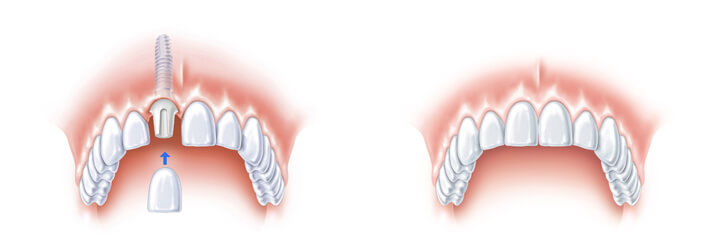

Bei Patienten, die beispielsweise durch einen Unfall einen Frontzahn verloren haben, ersetzen wir diesen durch ein Zahnimplantat. Häufig müssen auch durch Karies oder Wurzelbehandlungen die unteren Backenzähne entfernt werden. Vor allem bei

gesunden Nachbarzähnen, die sonst für eine Brücke beschliffen werden müssten, sind Zahnimplantate sehr sinnvoll.